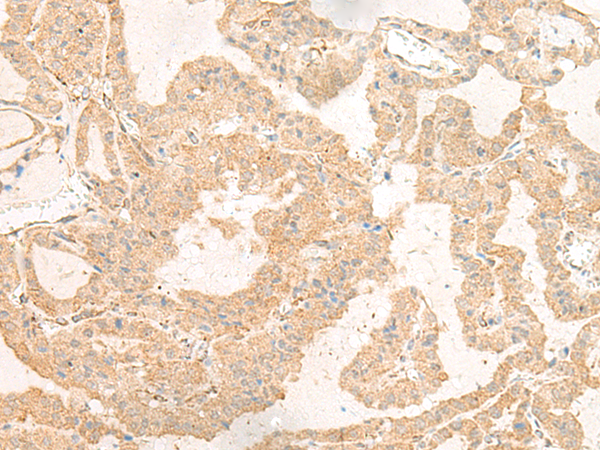

ELISA, IHC |

IHC positive control: |

Human thyroid cancer and Human esophagus cancer |